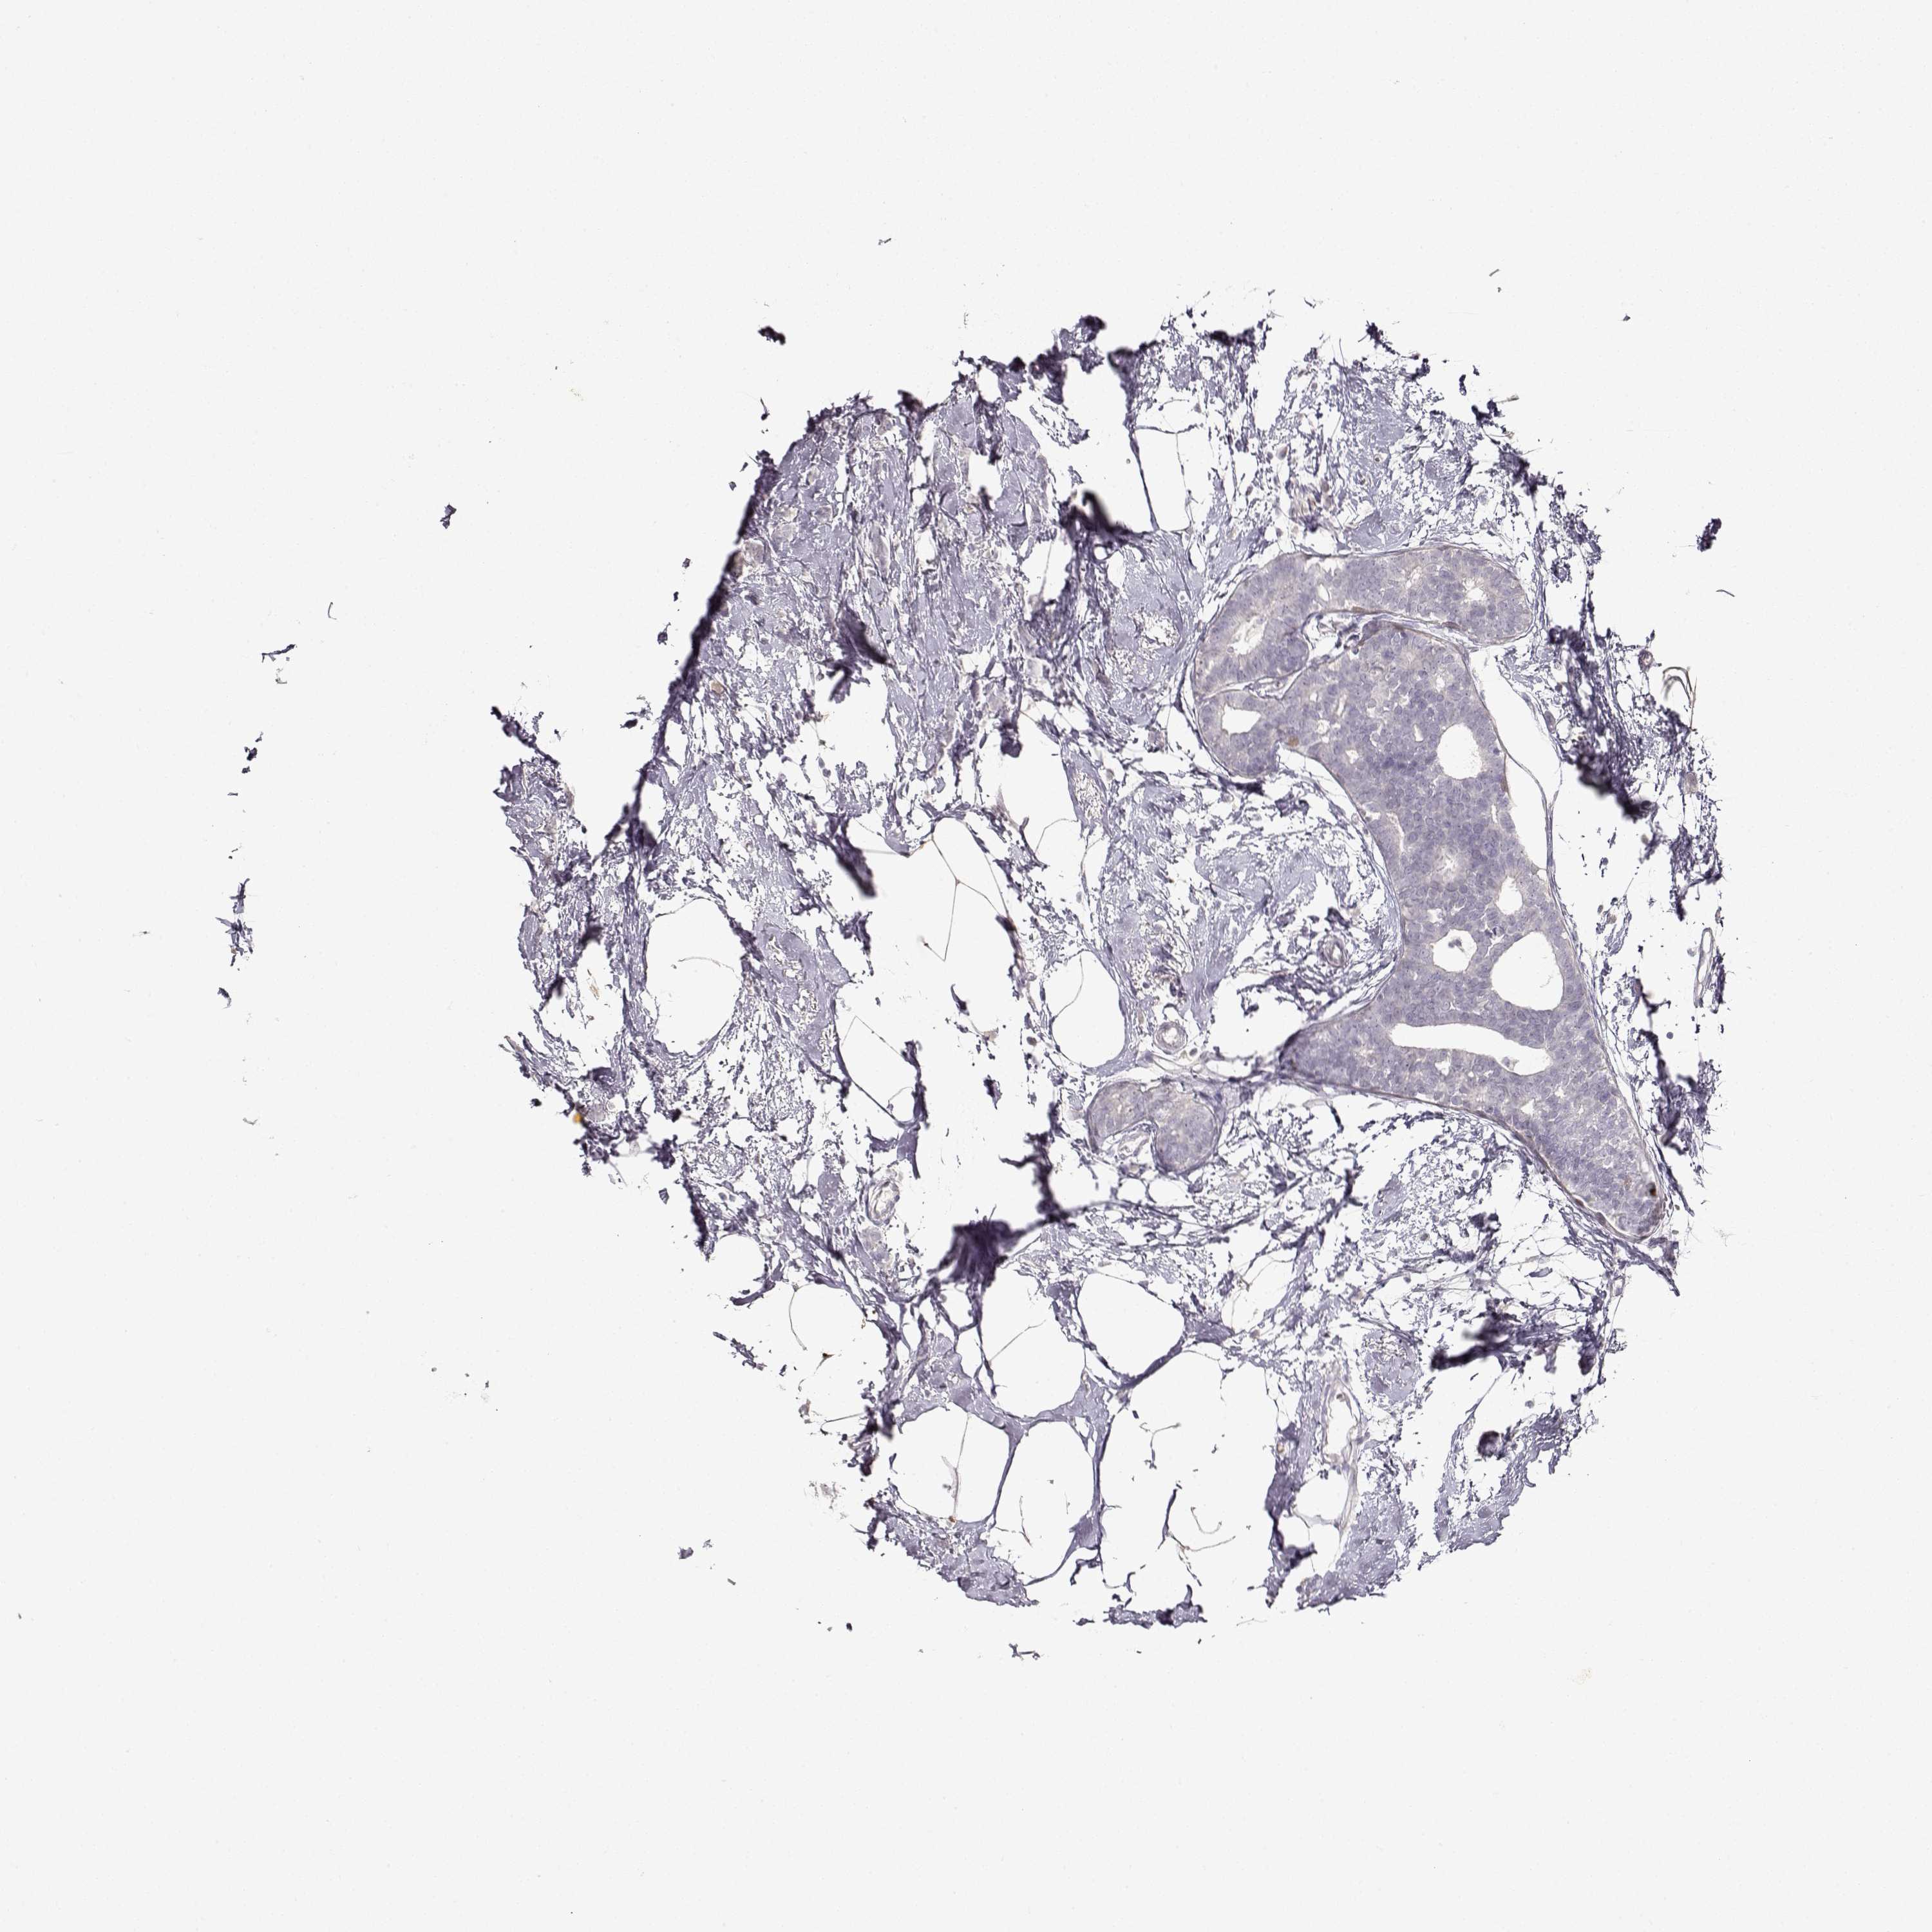

CANCER BREAST CANCER Show tissue menu

Breast cancer

Human cancer

S100B is not prognostic in Breast Invasive Carcinoma (TCGA)